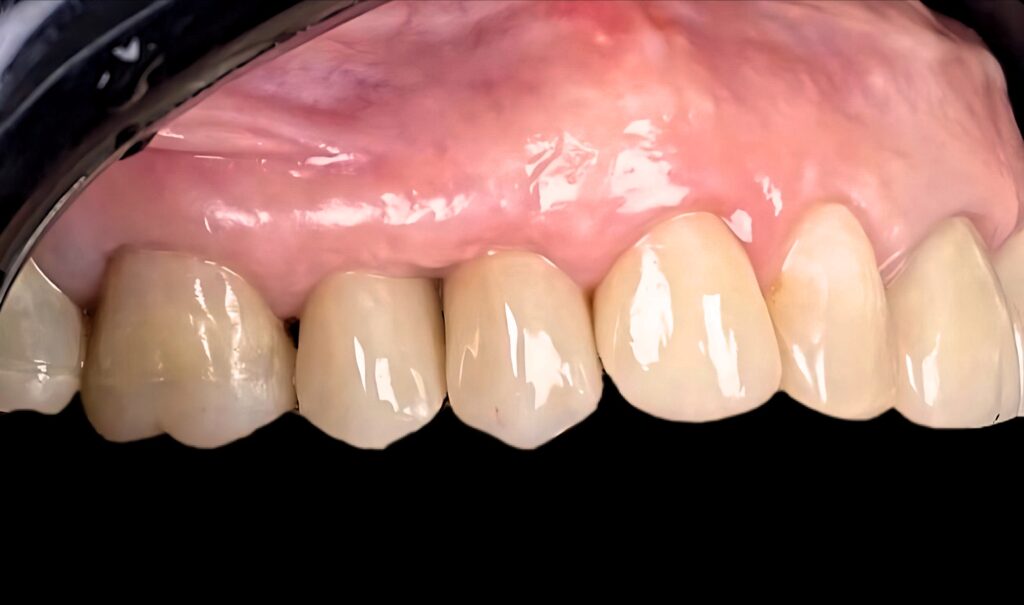

- Instalación de prótesis Fijas Unitarias de Zirconio monolítico Cut- Back Color 3M2 sobre pilares Tibase